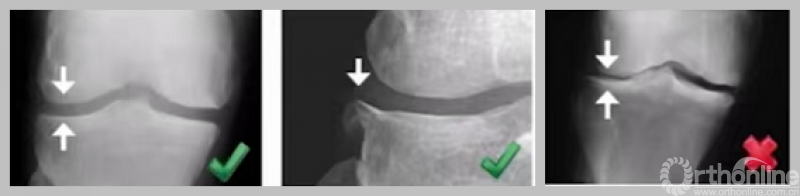

3. 外侧全层软骨完好

负重位及外翻应力位保证外侧间隙正常。

4. MCL功能正常

可复性关节内畸形,屈曲20°,外翻应力位X线片。